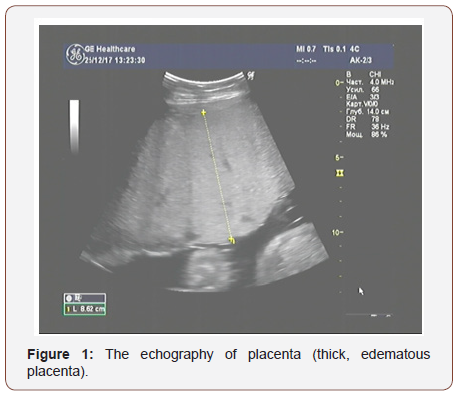

The results of ultrasound examination showed a single fetus in the uterus in the transverse position; in terms of its photometric parameters, the fetus fitted 31 weeks of gestation, the expectable estimated fetal weight was 1400 grams., a very thick placenta - up to 86mm (Figure 1) with medium echogenicity, multiple small anechoic structures (Figure 2), moderately expressed oligohydramnios (amniotic fluid index - 72mm) and a short neck uterus according to the results of cervicometry (20mm). Another feature is large, multichamber, an echogenic, bulky ovarian formations on both sides of the uterus (Figures 3&4). The size of the right ovary was 88 × 53 × 83mm, of the left one - 91 × 56 × 82mm. Hemodynamic disorders of the uteroplacental circulation were not detected.

Considering the data of ultrasonic examination of the fetoplacental complex and the revealed pathological changes, we noticed the signs of a trophoblastic disease (thick, swollen, cysticaltered placenta and echo graphic changes in the ovaries that indicate the presence of theca lutein cysts).